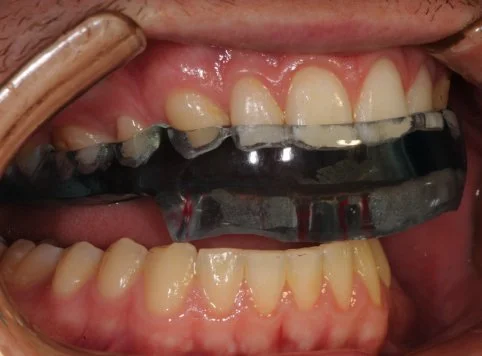

A TMJ Disorder patient requires conservative management with “Full Occlusal Therapy” in 3 stages along with concurrent Full Counselling (refer to journal papers 19 and 20).  In other words, we need to get the disc back into the centre of the joint where it belongs starting with Full Counselling and then a Fully Protective Occlusal Splint (Stage 1).  This splint is made of acrylic resin (used for dentures) and can be made in clear resin but is usually coloured blue or pink to hide any future discolouration (as in the photos below). The splint usually fits the upper teeth and only one is required.

Stage 1 - Fully Protective Occlusal Splint - 4 SA’s over a 3 month period

Stage 1 of Full Occlusal Therapy is Formal Fully Protective Occlusal Splint Therapy with case study